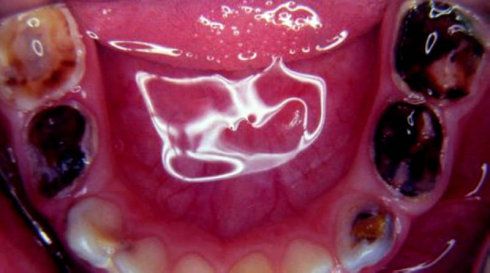

首先,蛀牙它黑啊,严重了牙齿还掉的一块一块的,能好看才怪呢!想一下,女神一张嘴牙齿是下边这个图,你表白一个我看看。

图片来源http://blog.sina.cn/dpool/blog/s/blog_8ec42ca3